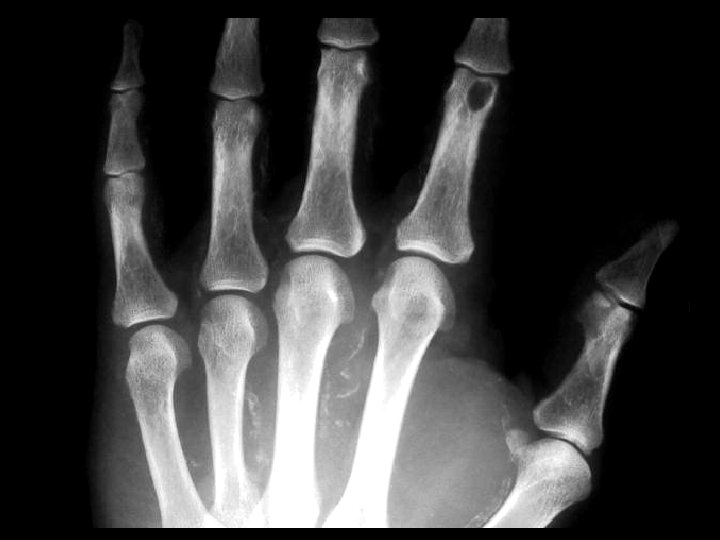

Enchondroma • Findings: – Lucent, slightly expansile lesion of the fifth MC • ddx: – Giant cell tumor – UBC – Fibrous dysplasia